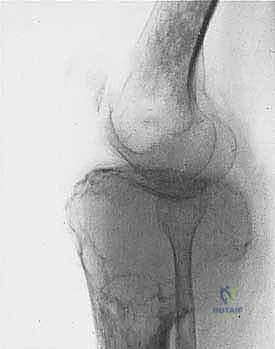

* الساركوما العظمية (Osteosarcoma): الأكثر شيوعاً، تظهر عادة حول الركبة (أسفل الفخذ أو أعلى القصبة).

| حدود الورم في الأشعة | واضحة، محددة بدقة (Sclerotic margin) | غير واضحة، متآكلة (Moth-eaten appearance) |

| اختراق قشرة العظم | نادر جداً | شائع جداً، يمتد للأنسجة الرخوة المحيطة |

2. الموقع (Site - T): هل الورم داخل الحيز العظمي (Intracompartmental - T1) أم اخترق القشرة وخرج للحيز الخارجي (Extracompartmental - T2)؟

المرحلة الثانية: إعادة البناء العظمي (Skeletal Reconstruction)

بعد إزالة جزء من العظم (أو المفصل بأكمله)، يجب سد الفجوة. تتعدد الخيارات التقنية التي يوفرها الدكتور هطيف في صنعاء:

1. المفاصل الصناعية الكبيرة (Megaprostheses): مفاصل معدنية متطورة (من التيتانيوم) تُصمم خصيصاً لتعويض العظم المفقود، وتسمح للمريض بالحركة المبكرة.

| المفاصل الصناعية (Megaprostheses) | استعادة الحركة فوراً، تأهيل سريع، لا تحتاج لانتظار التئام العظم | قد ترتخي مع مرور السنوات، تكلفة أعلى، عرضة للالتهابات | كبار السن، الأورام القريبة جداً من المفاصل (الركبة/الكتف) |